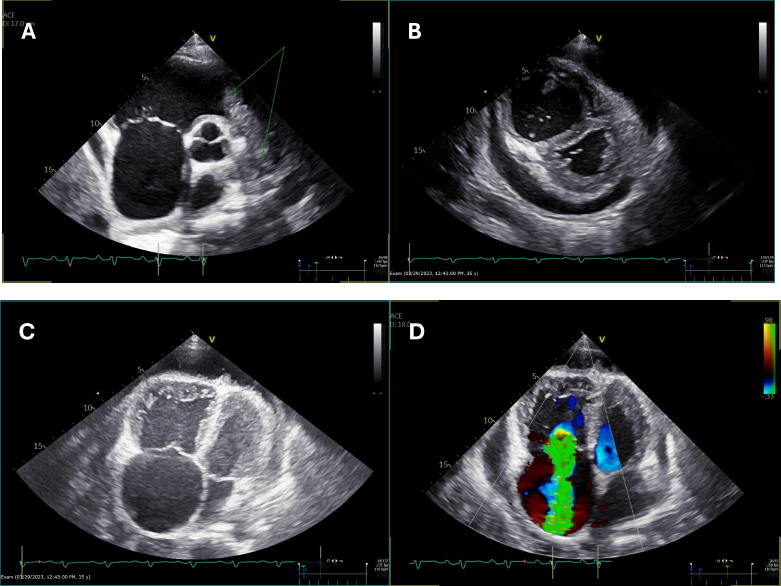

Initial echocardiography showed features suggestive of pulmonary embolism and right ventricular strain. There was suspicion of a mass at the level of the right ventricular outflow extending into the main and right pulmonary arteries. Mechanical thrombectomy followed by 72 h of catheter-directed thrombolysis was performed. However, the pulmonary angiogram continued to show a persistent filling defect after 72 h of thrombolysis. Serial follow-up echocardiography studies during his hospital stay revealed a low-normal left ventricular systolic function and an ejection fraction of 54%. The right ventricle and right atrium were severely dilated, the right ventricular systolic function was severely reduced, and severe tricuspid regurgitation was seen. A large mass was seen occupying the right ventricular outflow tract (RVOT) and main pulmonary artery, causing subtotal obstruction with only minimal flow (Fig. 1A-D), (Suppl: Video 1).

(A) Parasternal short-axis view at the level of the aortic valve showing a mass in the right ventricular outflow tract (RVOT) and pulmonary artery (double arrows), along with a dilated right atrium (single arrows).

(B) Parasternal short-axis view at the level of the papillary muscles demonstrating a D-shaped septum in systole, indicative of elevated right ventricular systolic pressure (RVSP), with a dilated right ventricle (RV). Pericardial effusion is also visible.

(C) Apical four-chamber view showing dilated right-sided chambers with the presence of pericardial effusion.

(D) Apical four-chamber view with color Doppler revealing severe tricuspid regurgitation.